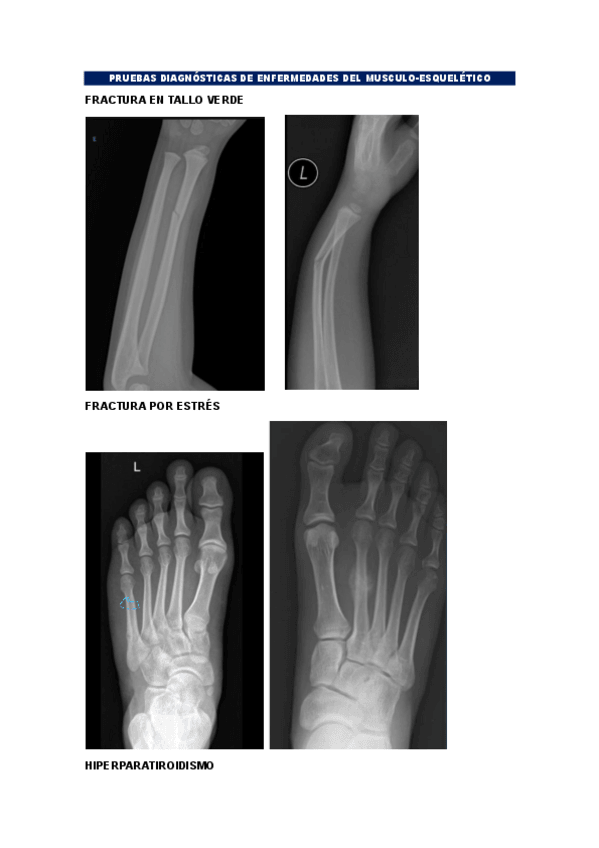

BLOQUE-MUSCULO-ESQUELETICO.pdf